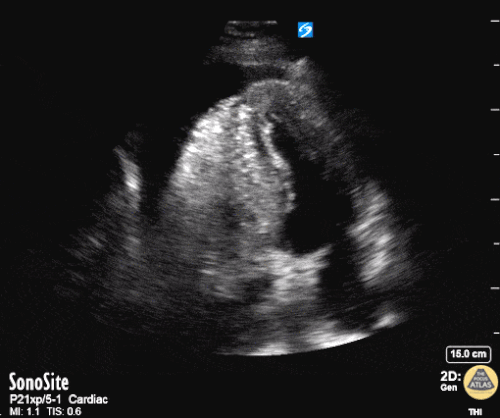

Pumpfunktion

Bei der Notfallechokardiographie geht es nicht um die genaue Berechnung der Ejektionsfraktion. Im Notfall geht es um drei Kategorien: gute (erhaltene) Pumpfunktion, schlechte Pumpfunktion, sehr schlechte Pumpfunktion. Dies wird visuell eingeschätzt. Es wird nichts gemessen – der erste Eindruck zählt. Auch Wandbewegungsstörungen können visuell erfasst werden.

Quelle: http://www.thepocusatlas.com/left-ventricle-1 CC BY-NC 4.0